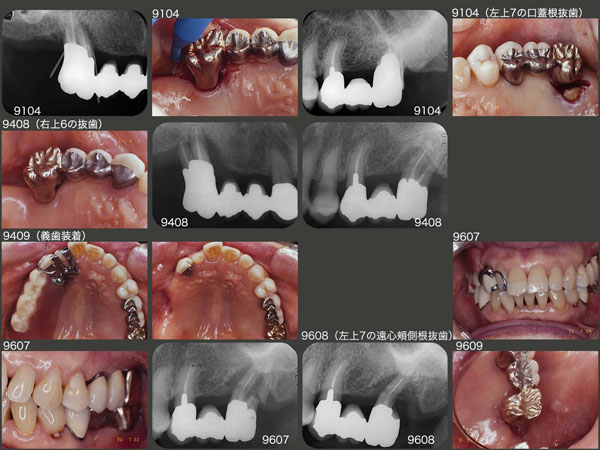

しかし,1991年4月,上顎左右大臼歯に問題が生じた.まず,右上6については,歯周病が悪化し,近心から遠心にかけて3度の根分岐部病変が認められた.左上7は,口蓋根に根尖まで達する歯周ポケットが認められたため,口蓋根を抜去した.

右上6は,騙し騙し使っていただいていたが,94年8月抜歯に至った.そこで右上に,簡単な片側処理の義歯を製作したが,あくまでも飾り物に過ぎず,患者さんは左側で咀嚼せざるを得なかった.

この状態で約2年過ごしていただいたが,今度は咀嚼側である左上7の遠心頰側根が歯根破折し,同根を抜去した.